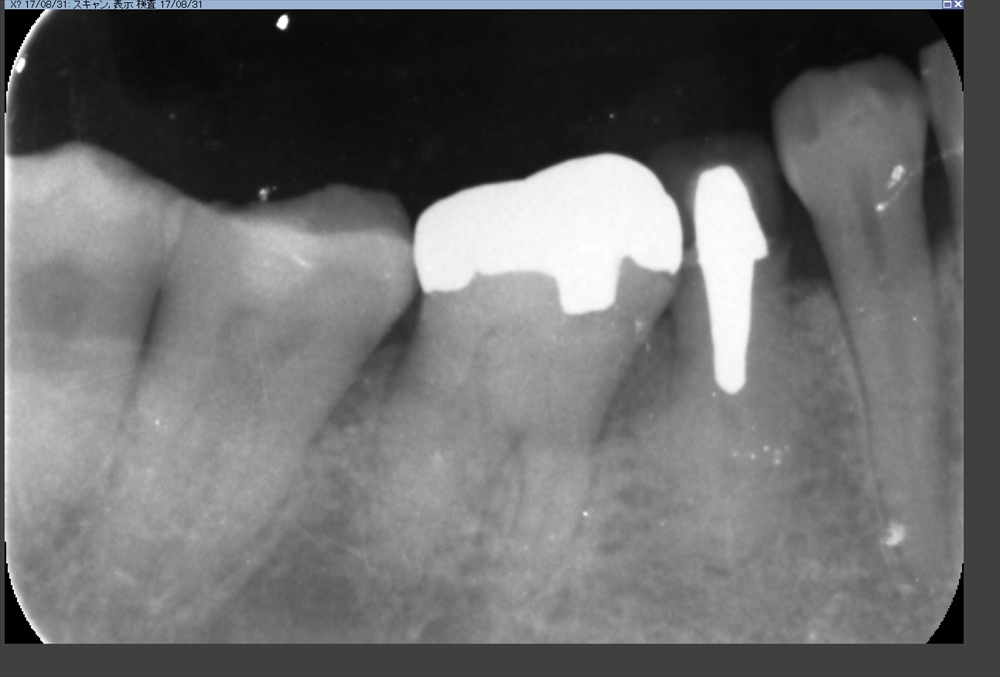

次のケースは今日で3回目の精密根管治療

綺麗になりました。症状もなくOK!!

ラストスパート

最終的なお薬を入れます。レーザー

よっこいしょ

術前

術後

次回から土台へGO!!